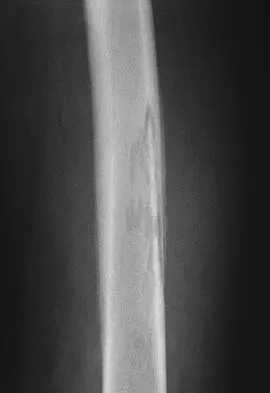

Question 14 High Yield

A 51-year-old woman has had progressively increasing right knee pain for the past 6 months. She has a history of metastatic renal cell carcinoma to the lung and the skeletal system. Radiographs are seen in Figures 18a and 18b. The next step in management of the right distal femur lesion should consist of

Detailed Explanation

In a patient with known metastatic disease, the surgeon must rule out additional lesions throughout the femur prior to surgical management. Lesions located in the diaphysis or in the peritrochanteric region may influence the surgical procedure. Frassica FJ, Gitelis S, Sim FH: Metastatic bone disease: General principles, pathophysiology, evaluation, and biopsy. Instr Course Lect 1992;41:293-300.